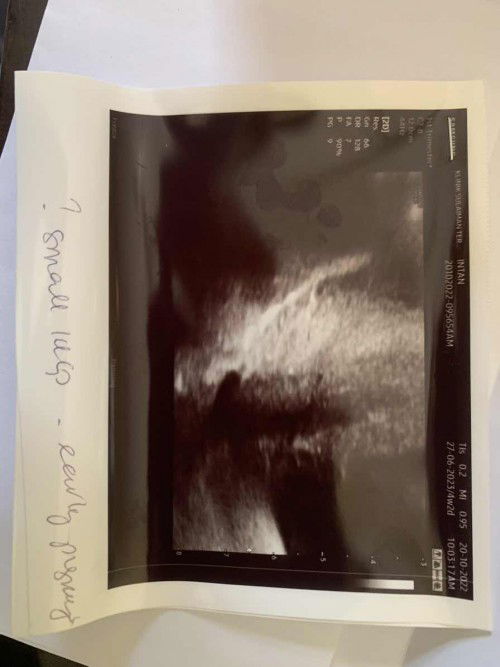

Scan 4 minggu

Hi. Nak tanya apa maksud small iucg?

Small iucgs = kantung size kecil,normal sebab baru 4weeks